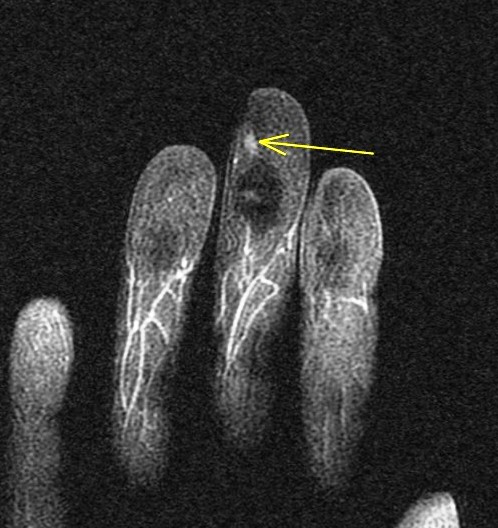

Figure 2 for case glomus tumor ( RID4513 )

Figure 2